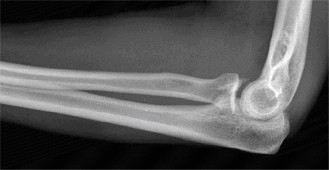

Treat a patient with infected total shoulder arthroplasty? CASE 21 A 70-year-old, right-hand-dominant female presents to clinic complaining of 4 years of gradually worsening chronic right shoulder pain and stiffness. She says the pain is worse at night and with any range of motion, denies a history of trauma, pain in other extremities, or numbness or tingling of the right upper extremity. She notes that her mother suffered from rheumatoid arthritis that affected her shoulder. Physical examination reveals decreased muscle bulk over the right supra- and infraspinatus fossae compared to the contralateral side, limited active and passive ROM, marked weakness with external rotation, and 4+/5 strength with shoulder abduction. X-rays of the right shoulder are shown in Figures 2–58 and 2–59.

Figure 2–58

Figure 2–59

The correct answer is (C). Rotator cuff tear arthropathy consists of a combination of rotator cuff insufficiency, glenohumeral joint degenerative changes, and superior humeral head migration. It is more common in women and also more often found on the dominant side. The patient’s clinical examination with weakened external

rotation and muscle atrophy signaling incompetent supra- and infraspinatus muscles point to rotator cuff insufficiency, and her plain films reveal narrowed glenohumeral joint space as well as superior migration of the humeral head. Choice D is incorrect because, while radiographs would show narrowing of the glenohumeral joint space, they would also likely show numerous osteophytes and posterior wear of the glenoid. Choice B is incorrect because, while adhesive capsulitis does present as decreased active and passive range of motion, the patient’s constellation of symptoms pointing towards rotator cuff insufficiency along with the radiographs make cuff tear arthropathy the more likely choice. Finally, Choice A is incorrect because even though she has a positive family history of rheumatoid arthritis, it is less likely to present only in a single joint. Also, rheumatoid arthritis on radiography appears more as an erosive process without the characteristic superior migration of the humeral head.

The correct answer is (A). Superior migration of the humeral head would be most indicative of chronic rotator cuff insufficiency associated with cuff tear arthropathy, as it is a direct result of the inability of the rotator cuff tendons to help maintain the humerus in its normal position. Acetabularization of the undersurface of the acromion is commonly associated with superior migration of the humeral head found in rotator cuff tear arthropathy, and can be assessed using the Hamada classification, which is based on measurements of the acromiohumeral interval on radiography (Table 2–8). Choices B and C are incorrect because, while narrowed glenohumeral joint space and subchondral sclerosis are associated with rotator cuff arthropathy on radiographs, they indicate degenerative joint changes rather than chronic rotator cuff insufficiency. Choice D is incorrect because it is not a specific sign of rotator cuff arthropathy.